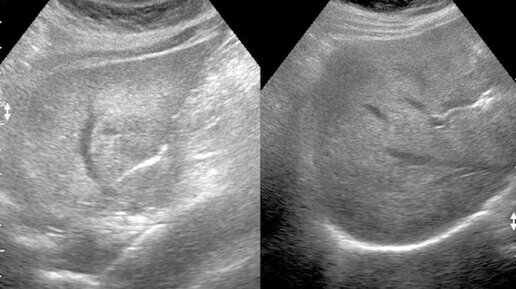

Диффузные изменения перенхимы печени и жировой гептоз на УЗИ - что это значит? Объясняю на примерах

Скажу сразу, что это очень простой и одновременно сложный вопрос. Если объяснять совсем в лоб, то словосочетание "диффузные изменения печени переводится следующим образом": "на УЗИ ваша печень отличается от здоровой, но каких-то катастрофических изменений нет, как и конкретного диагноза"...